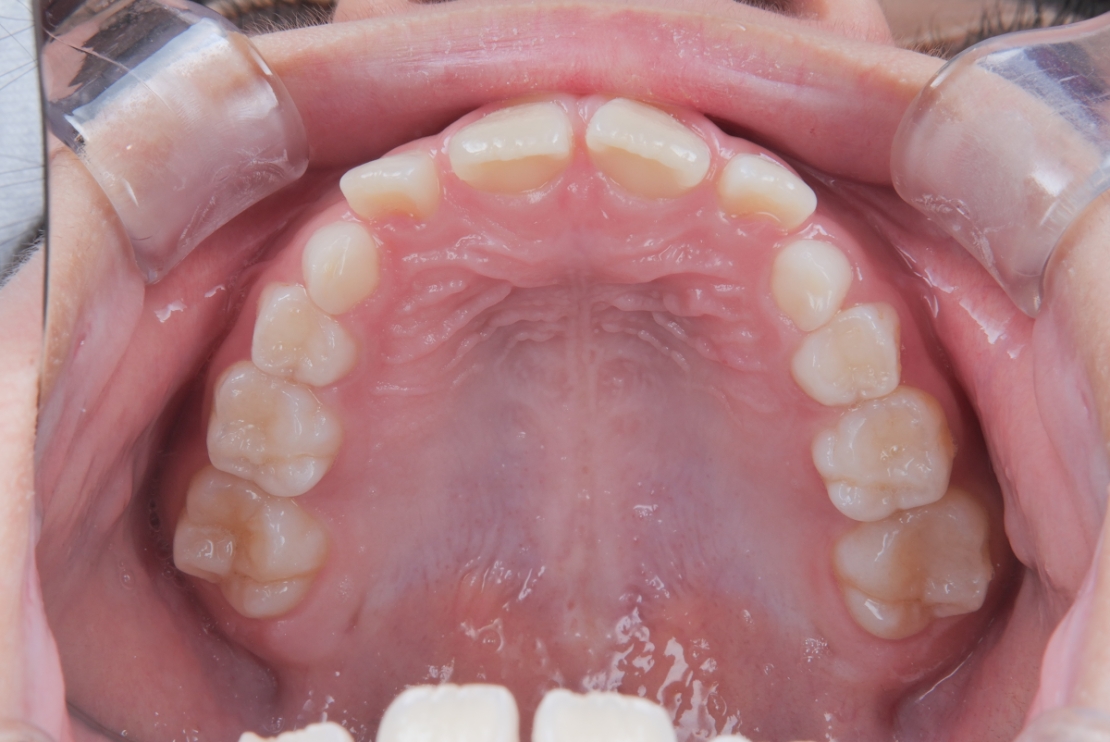

BEFORE

スタート時8歳の女の子の症例です。主訴は歯並びのガタつきと、上の2番目の歯が八重歯のようにハの字に傾いていることでした。

治療は、マウスピース矯正インビザライン・ファーストにて矯正治療を行い、成長を活かしながら歯列を整えていきました。治療期間はわずか11ヶ月で完了し、ガタつきと歯の傾きは改善しています。